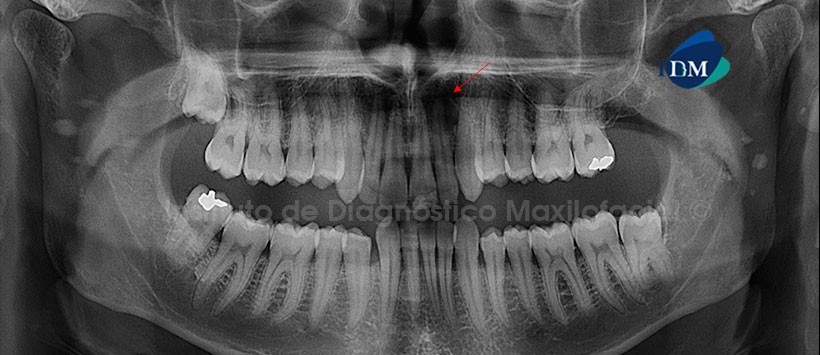

Paciente femenina de 29 años de edad que es referida para la evaluación de los terceros molares. La radiografía panorámica nos muestra la presencia de una imagen radiolúcida localizada en la región anterior del maxilar superior del lado izquierdo y que se encuentra aparentemente asociada a la raíz de la pieza 22, la misma que no presenta alteración a nivel coronario. Signos radiográficos sugestivos de una lesión perirradicular. Por otro lado, se aprecian: el aplanamiento del contorno de los cóndilos mandibulares, neumatización alveolar de los senos maxilares, las piezas 18 y 38 en estrecha relación con estructuras anatómicas circundantes y la mineralización de tejidos blandos proyectados sobre la rama ascendente mandibular compatibles con Tonsilolitos (Fig. 1).

La tomografía computarizada de haz cónico mediante los cortes transaxiales y tangenciales nos muestra claramente que la lesión perirradicular no sólo compromete la región de las pieza 22, sino que además se extiende hasta la región de la pieza 21. Así mismo, la lesión ocasiona el desplazamiento y erosión de la tabla ósea bucal. Signos imagenológicos sugestivos de un Quiste Radicular (Fig. 2 y 3).